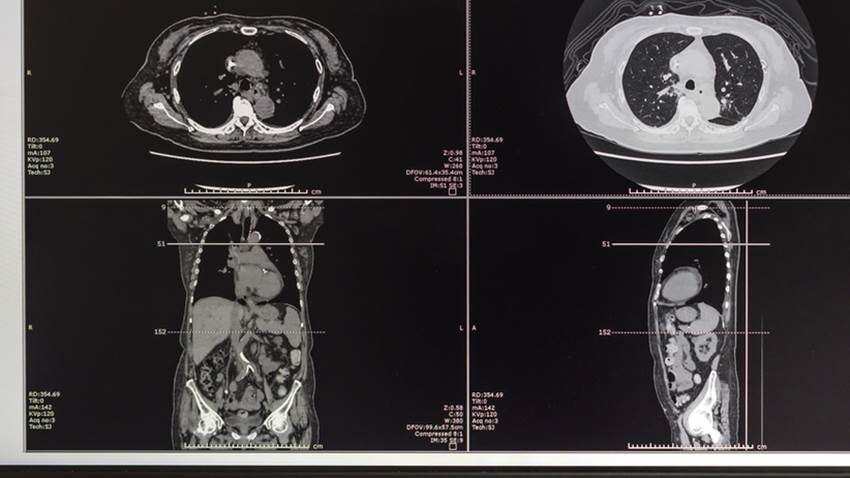

Descubren un Linfoma de Burkitt en paciente puertorriqueño sin síntomas

Este paciente de 52 años arribó a la sala de emergencias por una masa en su axila izquierda. El hombre tenía historial de hipertensión, apnea del sueñ...